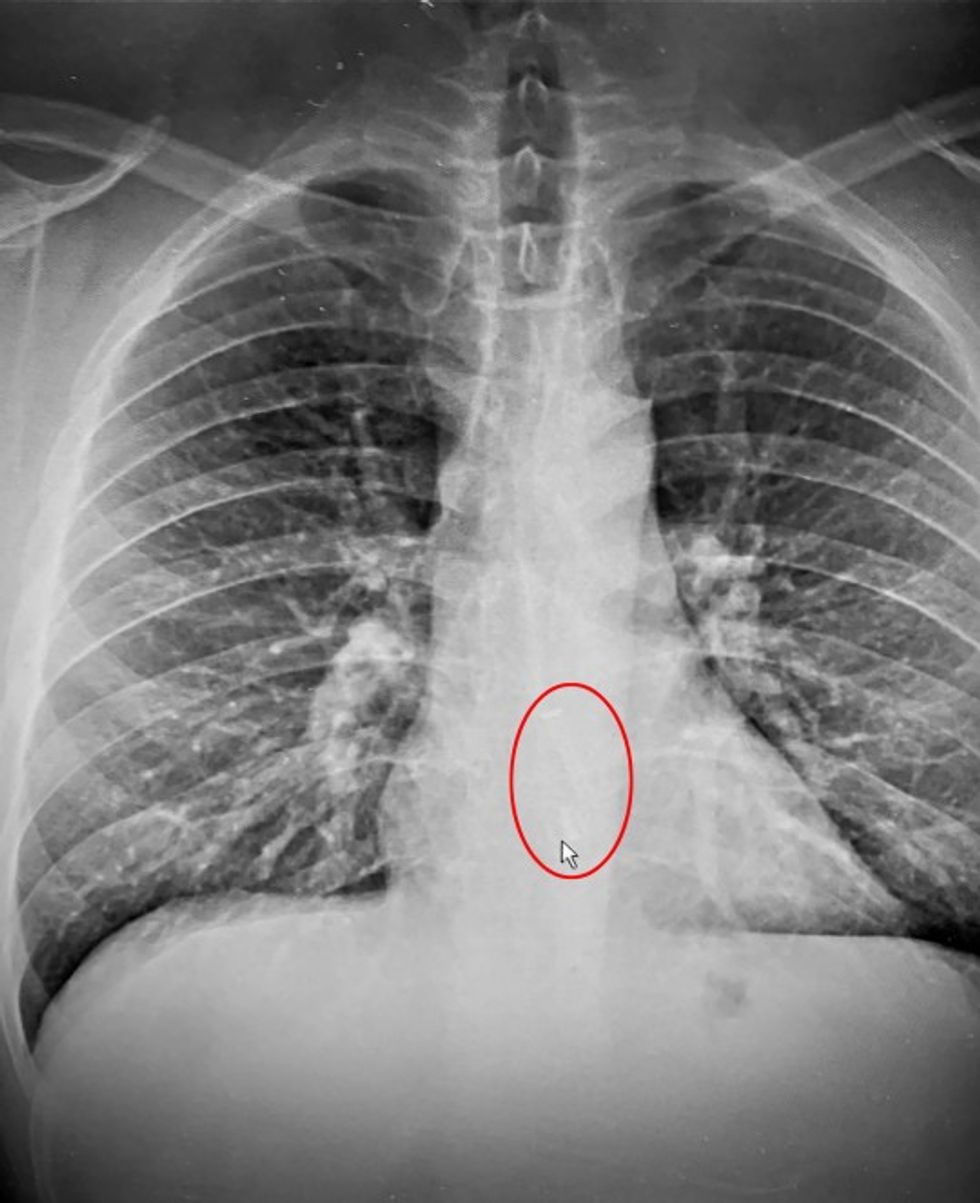

Megjithatë, rrezet X shpejt provuan që kjo ishte gabim.

Në foto shihet se burri kishte gëlltitur kufjen gjatë gjumit, dhe se si kishte ndodhur kjo ai assesi nuk e dinte.